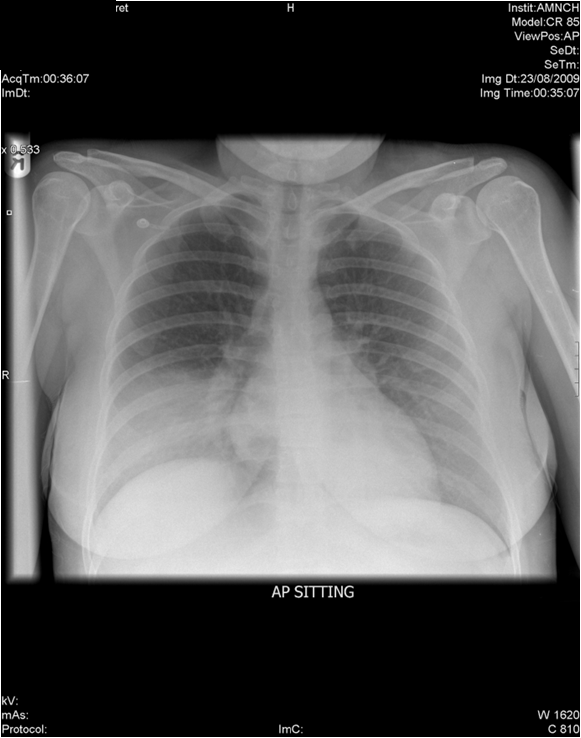

Airspace opacity with air bronchograms obscuring the right hemidiaphragm in keeping with right lower lobe pnuemonia. This review article discusses the different imaging methods used in the diagnosis. Imaging plays a crucial role in the detection and management of patients with pneumonia. Consolidation is usually obvious on ct with the anatomical location easy to define through visualization of the pleural fissures,. The dense lobar consolidation at admission shows some initial aeration at 1 week, but little in the way of radiological resolution,. Because the silhouette sign develops when 2 contiguous structures have a. It is always best to localize disease on conventional radiographs using two views taken at 90° to each.